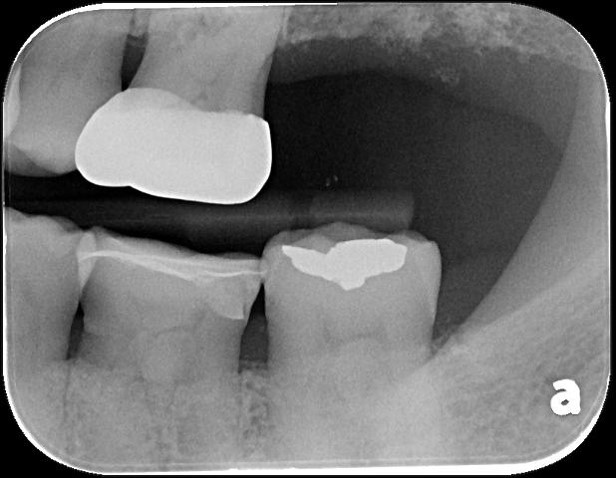

治療前,牙髓仍未受侵犯

陶瓷冠塊體製備